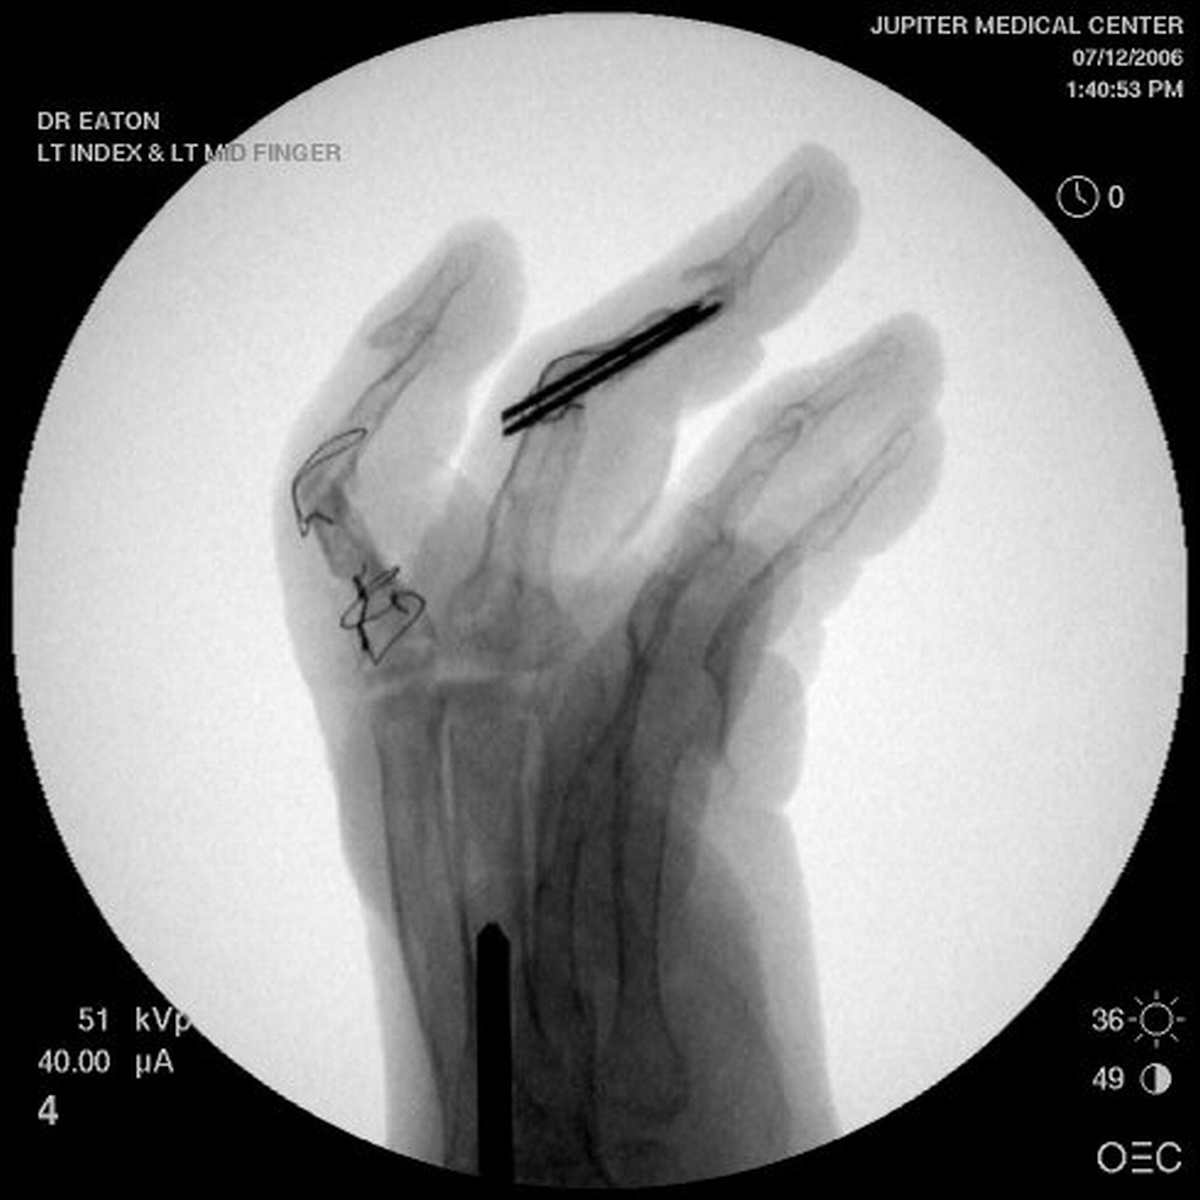

Final radiographs, three months postoperative.

For the second stage of her reconstruction, the index proximal phalanx did not have adequate dorsal cortex to support an implant arthroplasty, and bone graft from the metacarpal head was used to reconstruct this.

The technique is shown in this video.